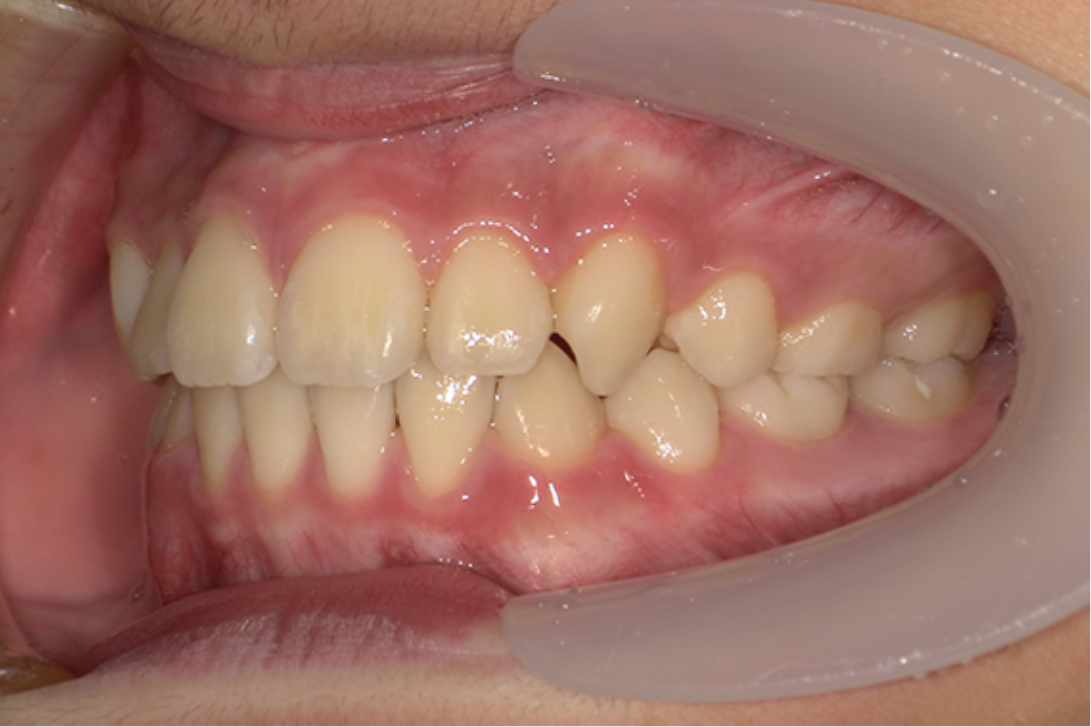

• 治療前

• 治療後

主訴:八重歯

診断:叢生

治療内容:唇側矯正治療

年齢:16歳

治療に用いた装置:マルチブラケット装置

抜歯or非抜歯:抜歯(上下顎両側小臼歯)

期間:14ヶ月

回数:14回

費用:957,000円(税込)

リスク・副作用:虫歯、歯肉炎、歯肉退縮、歯根吸収、後戻りなど